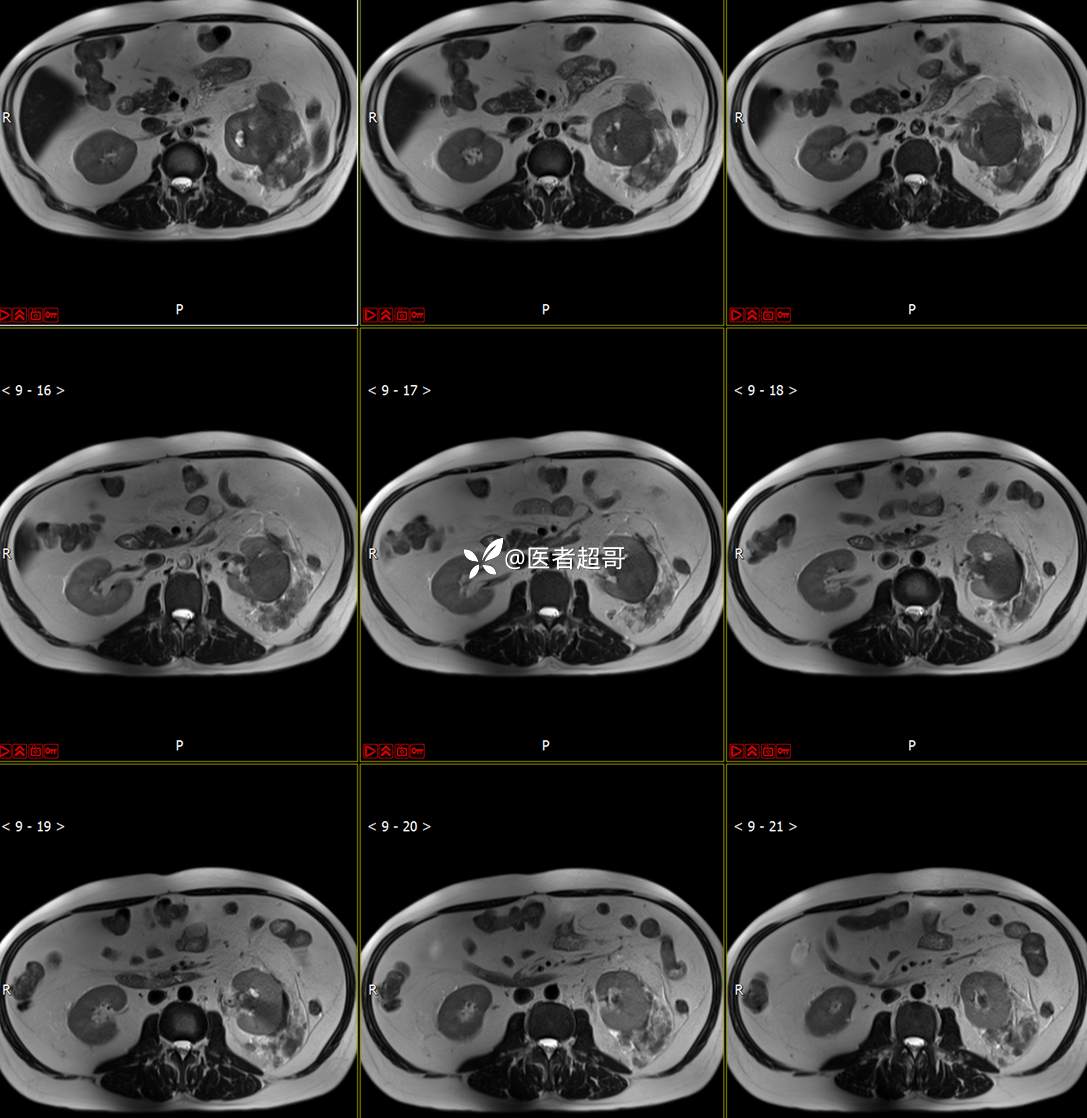

主 诉:查体发现左肾肿物9天。

现病史:患者9天前于附属医院行常规腹部CT检查时,发现左肾占位性病变并肾周脂间隙软组织增多,自述无明显腰腹部不适,无尿频、尿急、尿痛及肉眼血尿,未予特殊治疗,患者近期无头晕头迷,胸闷气急,腹胀腹泻及其他部位明显不适,遂至我院就诊,门诊以“肾肿物”收入院,患者自发病以来,精神可,睡眠饮食可,大便正常,体重无明显减轻。